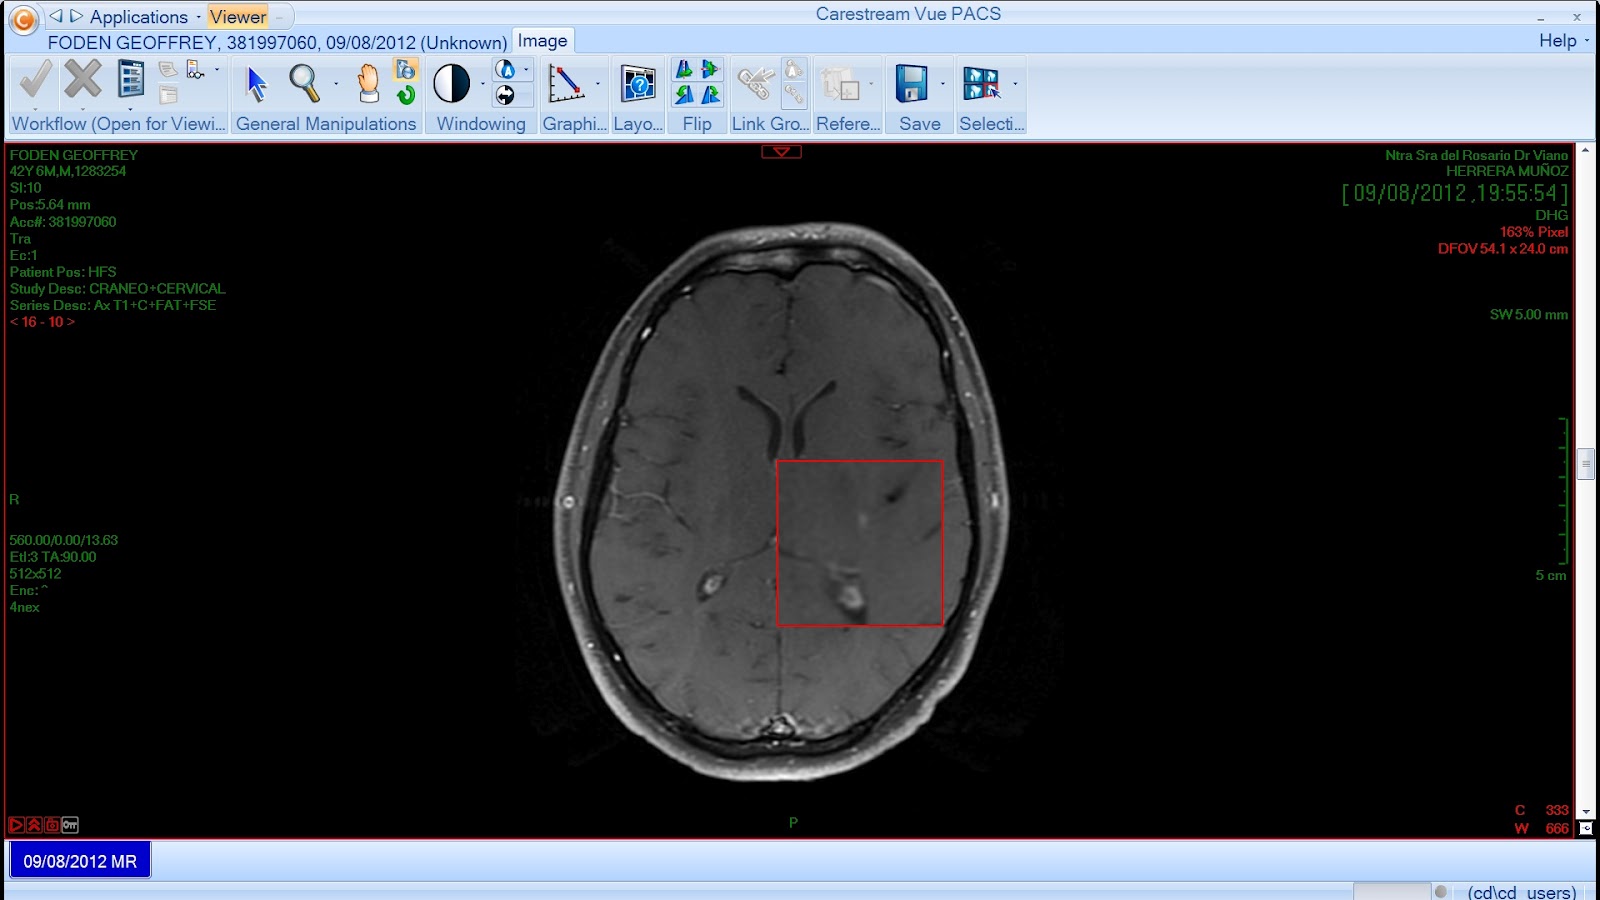

Hey pop-pickers, how'd you like a look at my Axial Flair MRI scan...

Hmm, not the most endearing pick-up line but here it is:

He went through the old scans and then followed up by examining the latest ones, and then he seemed to look a little concerned - I asked him what the matter was.

"Well, it looks like there is a new active lesion here in the new scans that wasn't in the old ones"

Dr Casals went back to the older scans.

"Ahhh, found it.", he said. "I must have missed it on the first pass. Well, if it had been a new lesion, that would have been bad news, however, it seems to be the previous one which might still have been active in the last three months so...there's nothing to worry about."